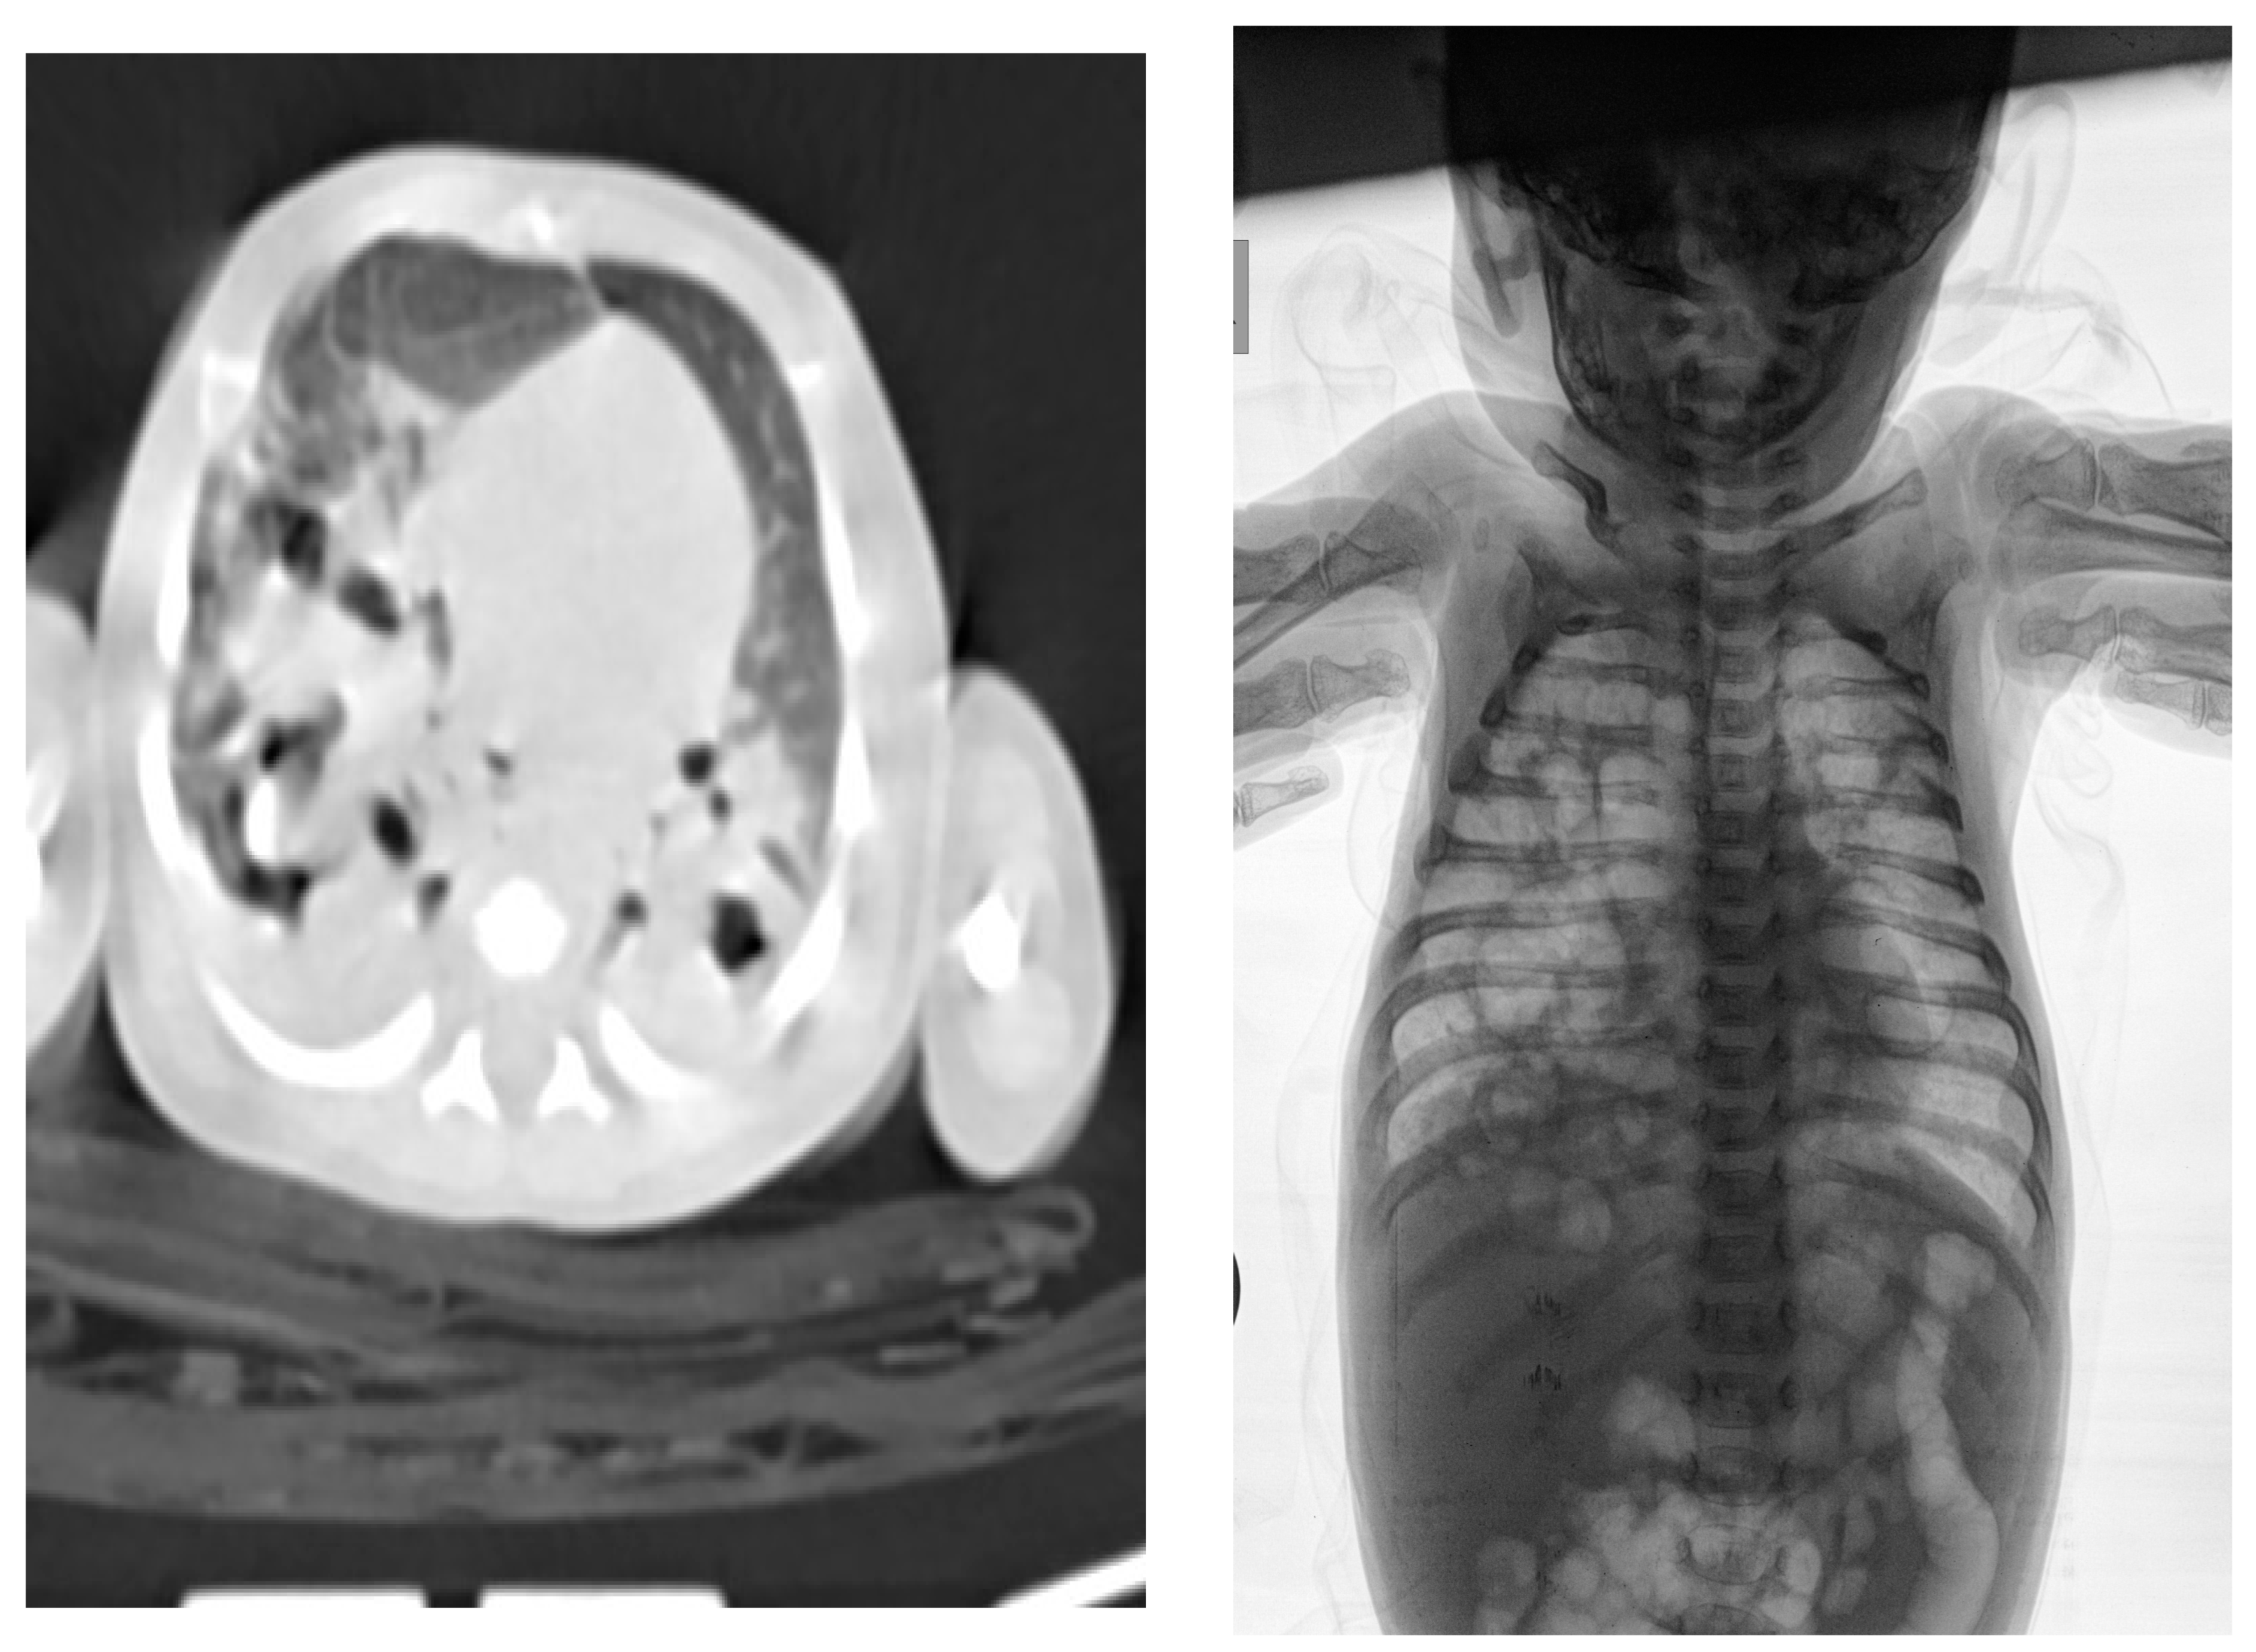

| Clinical picture at admission in Pediatric Clinic UCC | NN1 had a preserved sensorium, was high febrile 39.4 °C (rectal), with tachy-dyspnea, sobs, and moans, indents jugulum, dissatisfied cries, TM 4050 g, subclinical jaundice of the skin, and visible mucosa. Auscultation revealed attenuated respiratory sound, diffusely fine crackles, SaO2 82%, R 56/min, F 196/min. The umbilical stump persisted, the surrounding skin became red and swollen, there was hypotonia of the body axis, large fontanelle within the bony borders, greatness 20 × 30 mm. The other physical findings were normal. | NN2 had the preserved sensorium, was afebrile 37.7 °C (rectal), TM 3920 g, eupnoeic, presented sobs and moans, plethoric and icteric skin, nasal vestibules filled with seromucous secretion, and hyperemic throat. Auscultatory revealed a normal breathing sound is heard with transmitted wheezes from the upper parts of the airways and systolic murmur of 1-2/6 according to Levin, SaO2 97%, R 32/min, F 168/min. The umbilical stump persisted, thin, and the borders developed a serous–hemorrhagic discharge. There was mild hypotonia of the shoulder girdle and trunk axis, primitive reflexes were slowly elicited, large fontanelle was below the plane of the bony borders, and slightly spaced sutures, greatness 40 × 40 mm. The other physical findings were normal. |

| Tracheal aspirate by RT-PCR testing | Legionella pneumophila serogroup 2-15 | Legionella pneumophila serogroup 2-15 | |

| Culture of tracheal aspirate on the GVPC nutrient media | Legionella pneumophila, Pseudomanas aeriginosa | Legionella pneumophila | |